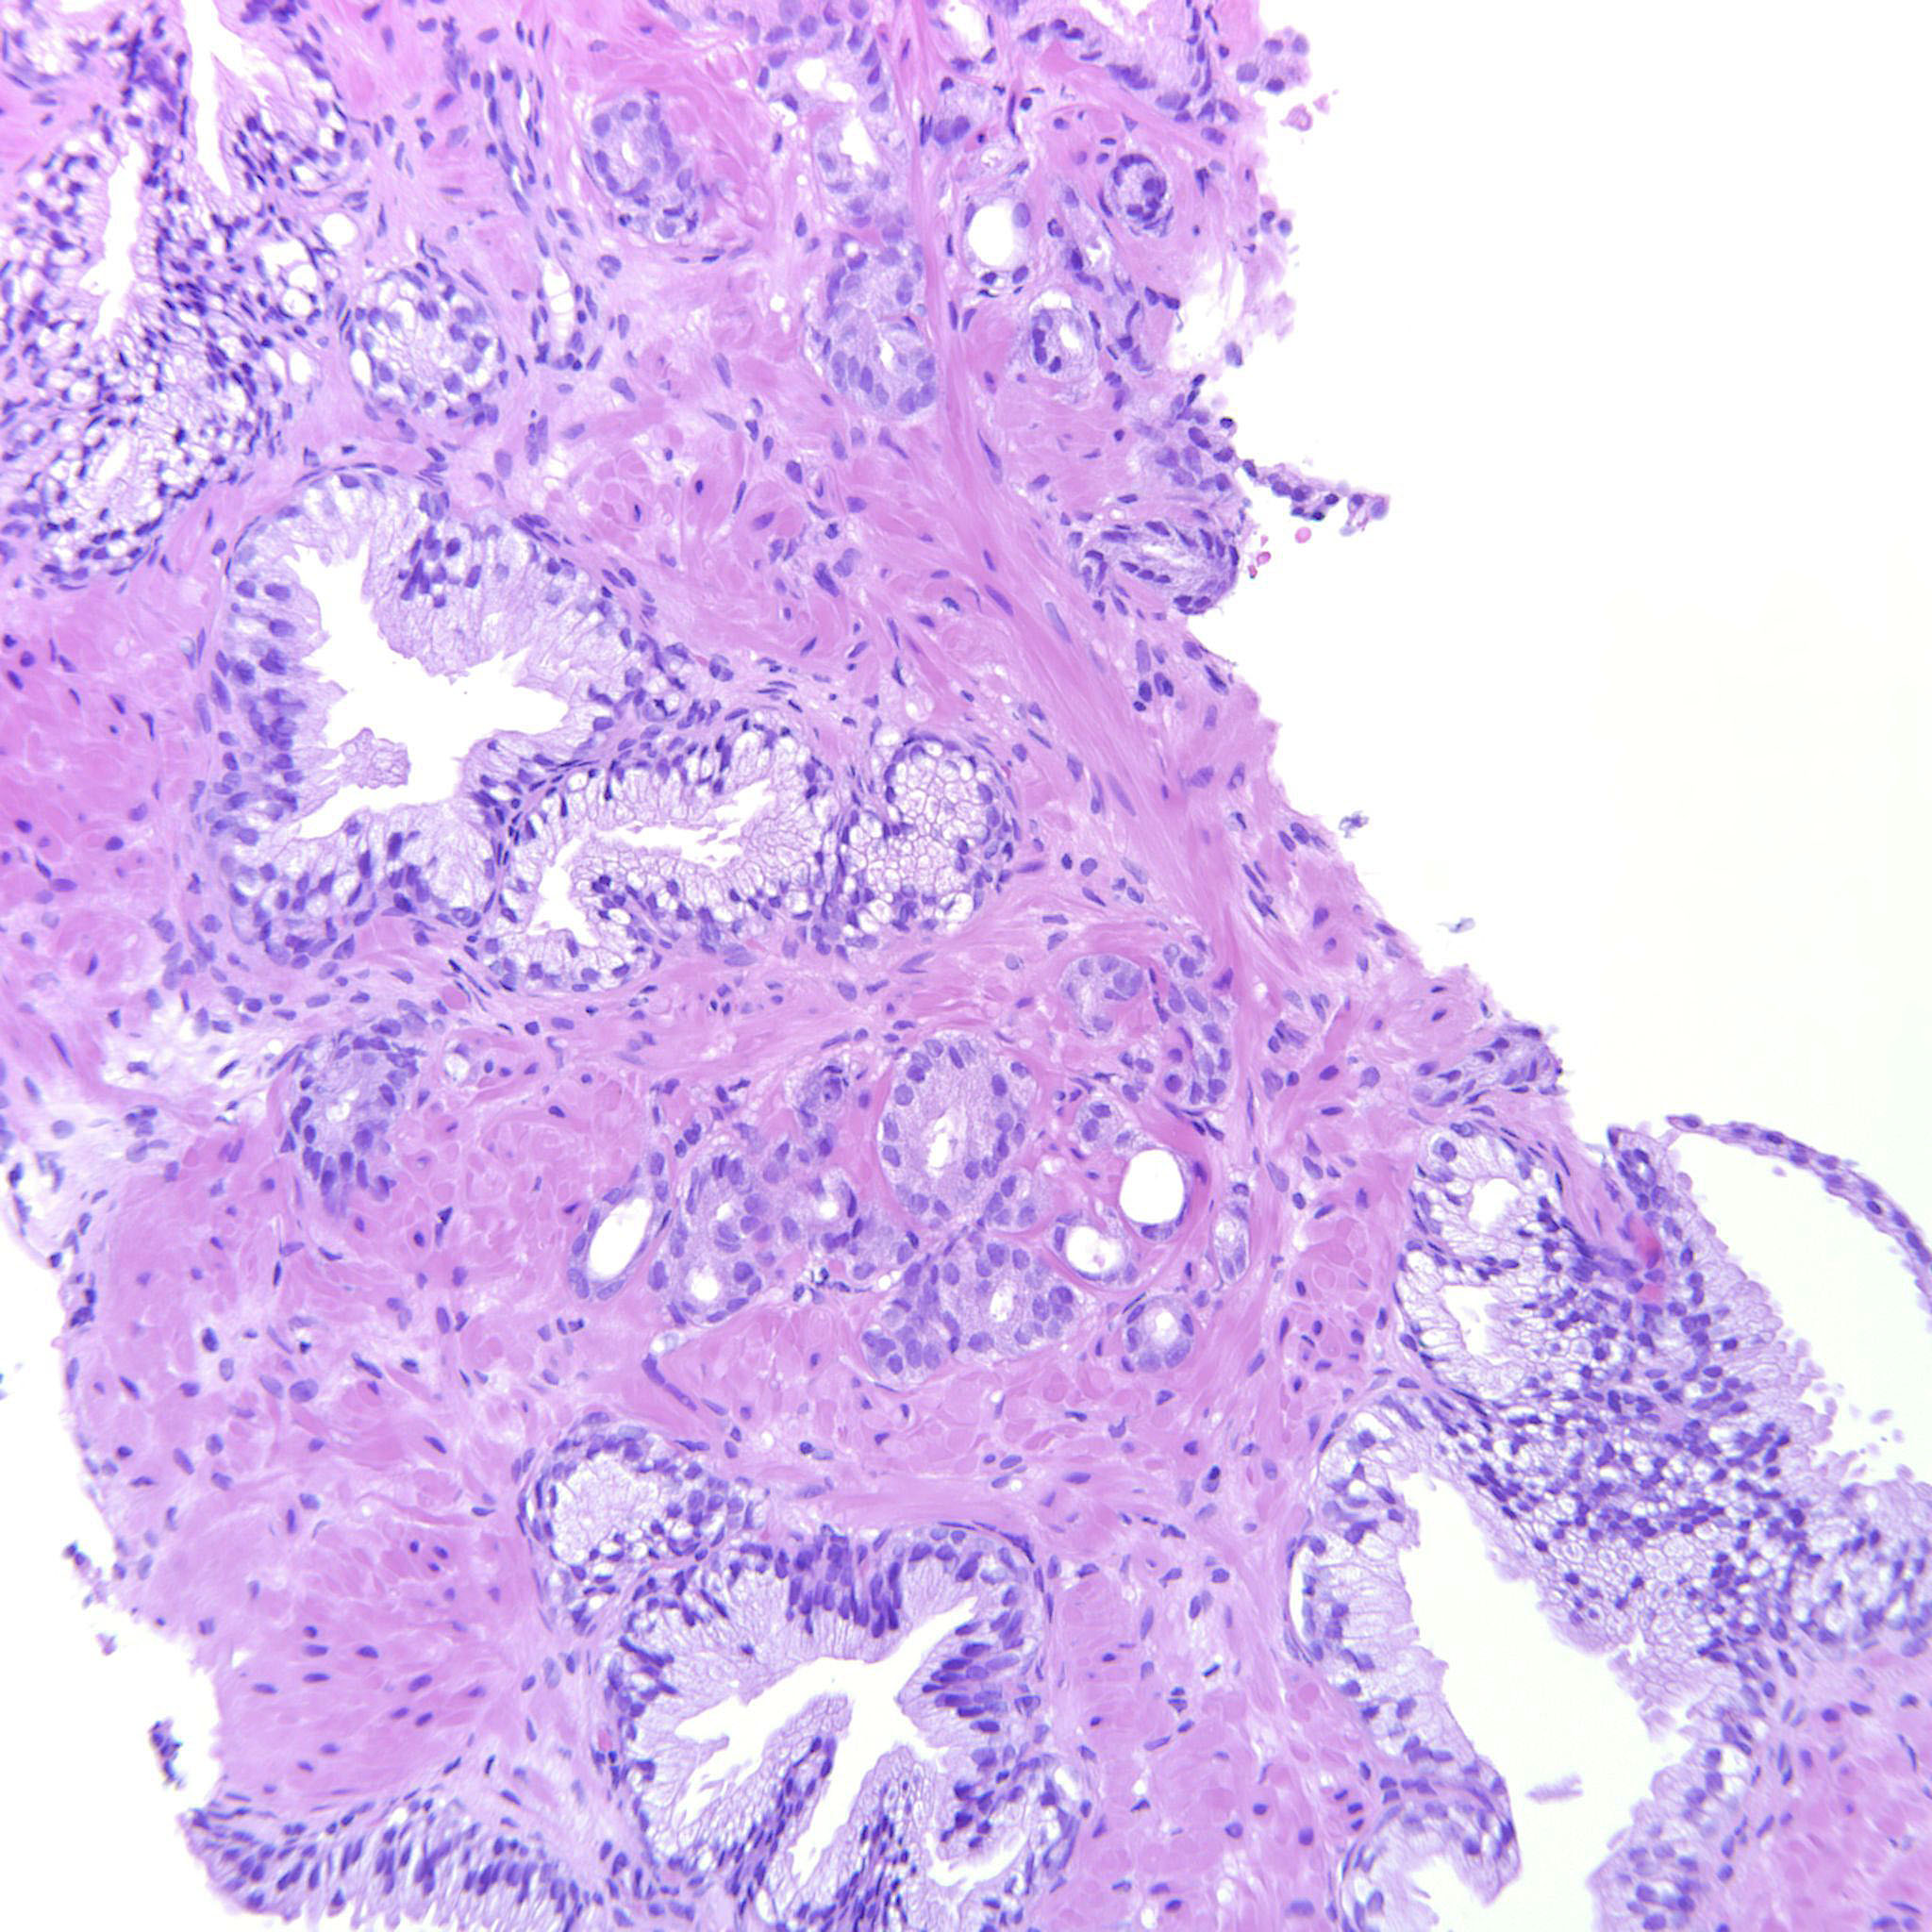

Prostate cancer grading

Case ID: 480